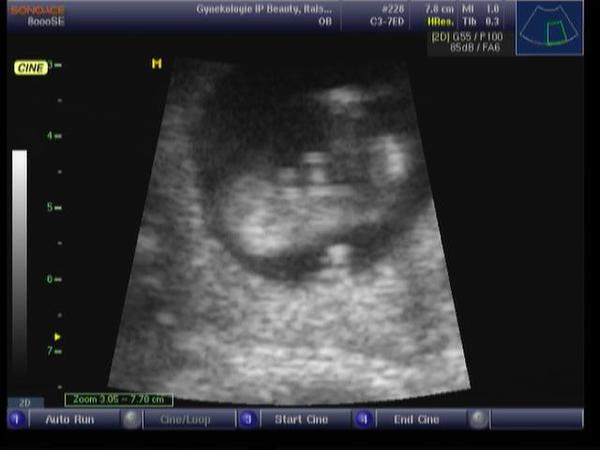

@aletheia Já se také přikláním k holčičce, ale sama jsem se tady ptala na pohlaví 😀 😀 😀

@barbucha123 A ty uz vis, jestli chlapecek/holcicka? U tebe bych rekla kluka, ale ja jsem slepa jak patrona 🙂

@aletheia doktor ve 20. tydnu rikal chlapecek, ale nejak se nemuzu zbavit pocitu ze to je holcicka 😀 tak sem se chtela ujistit tady 🙂 a jak je to tedy u Tebe? Trefili jsme se? 😀

@barbucha123 Nejspis ano 😀 Prof. tvrdil jasna holcicka, my jsme moc radi hlavne za zdrave mimco, ale naprosto kazdy me tipoval na kluka a ja si rekla proc ne a uz tak nejak zila predstavou klucika, tak se mi tomu nechce verit 🙂. Ale fakt je, ze mit holcicku alespon jednu, byl muj sen odjakziva 🙂 Tak snad nebude jeste prekvapko 😀